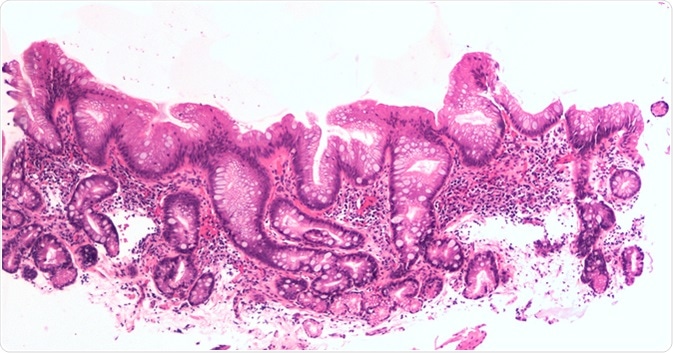

Intestinal metaplasia of the esophagus, aka Barrett's, is a response to injury due to acid reflux. Image Credit: David Litman / Shutterstock